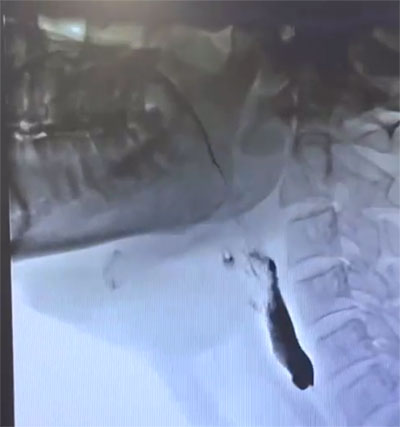

Modified Barium Swallow Study (MBSS) is considered the gold-standard procedure in assessing swallowing function. It is an x-ray/ fluoroscopic evaluation used to assess swallowing. Various texture and consistency food coated with barium are administered and swallowing is assessed. It is extremely helpful in diagnosing motility disorders affecting swallowing.

These diagnostic tests are conducted in the Radiology Department at our attached hospitals by our well trained swallowing therapist.